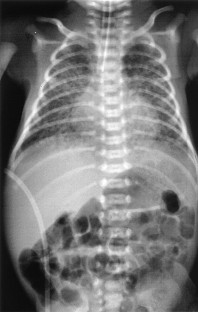

KL-6 and surfactant protein D (SP-D) serum concentrations are known to rise in adult patients with various types of interstitial pneumonia. We evaluated the time course of serum KL-6, SP-D, and lactate dehydrogenase (LDH) levels in an infant with Wilson-Mikity syndrome. In this case, serum KL-6 levels correlated with clinical symptoms better than serum SP-D and LDH levels. The findings of this case suggest that high serum levels of KL-6 show activity of interstitial lung disease of Wilson-Mikity syndrome.

Takami, T., Kumada, A., Takei, Y. et al. A Case of Wilson-Mikity Syndrome With High Serum KL-6 Levels. J Perinatol 23, 56–58 (2003). https://doi.org/10.1038/sj.jp.7210830